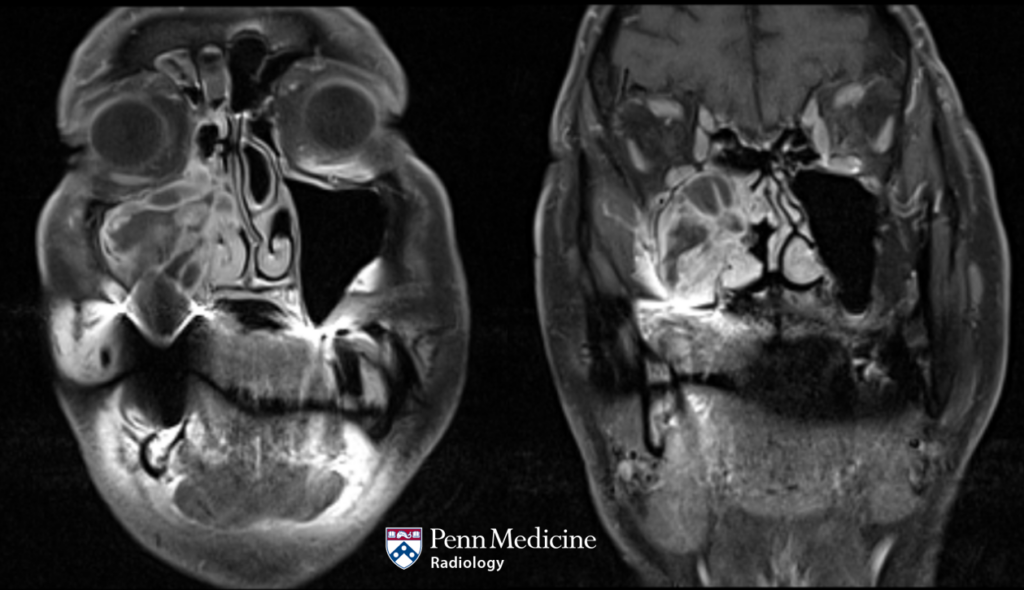

68-year-old man with unsteady gait and headaches

A 68-year-old man with a prior history of brain surgery presented with unsteady gait and occasional headaches.